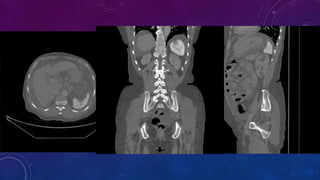

• Small well-defined round osseous lesions in the left

side of the abdomen, adjacent to midline represent

calcified lymph node in the para-aortic and left

common iliac groups, also visualized on the

corresponding CT.